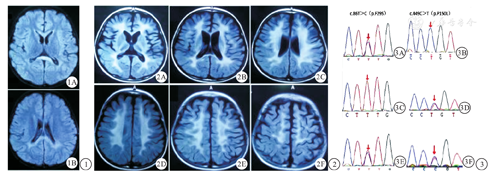

患儿 男,4岁半,第1胎。2岁前生长发育正常,2岁时无明显诱因出现进行性抬头不稳,头略后仰,翻身不能,拉起反射阳性,双侧膝腱反射活跃,双侧巴宾斯基征阳性,四肢肌张力高。头部磁共振成像(MRI)平扫可见胼胝体压部及双侧侧脑室后角旁白质区对称分布片状异常信号,为T1WI呈稍低信号,T2WI级压水压脂像呈稍高信号(图1)。双侧额、颞叶脑沟略增宽。提示髓鞘发育不良。临床诊断为脑白质发育不良,于我院康复科规律康复治疗。4岁时无明显诱因出现抽搐,发作表现为双眼上翻,凝视,口周发绀,四肢僵直,意识丧失。视频脑电检测可见背景弥漫性慢波,清醒期前头部偶见棘波散发。抽搐发生后立即就诊于我院,复查头部MRI可见双侧侧脑室旁白质区见对称性大片异常信号,T1WI呈稍低信号,T2WI级压水压脂像呈稍高信号(图2)。胼胝体体积变小,部分脑沟增宽。2个月前时患儿复查未出现其他系统异常表现,检测外周血白细胞芳香基硫酸酯酶A(arylsulfatase,ARSA)活性结果为32.6nmol/mg.17h(正常参考值217~360 nmol/mg.17h)。明确诊断为晚婴型异染性脑白质营养不良(metachromatic leukodystrophy,MLD)。父母体健,非近亲婚配,否认癫痫及遗传病家族史。其母现孕15周,于本中心行遗传咨询及产前诊断。

经知情同意后,采集患儿及其父母外周血进行脑白质病相关致病基因检测。结果显示患儿ARSA基因存在c.86T>C(p.Phe29Ser)和c.449C>T(p.Pro150Leu)位点复合杂合变异(图3)。患儿父亲携带c.86T>C(p.Phe29Ser)变异,患儿母亲携带c.449C>T(p.Pro150Leu)变异。患儿母亲于18周行羊水穿刺,羊水样本基因检测结果提示胎儿存在与患儿相同变异,经遗传咨询告知夫妇双方胎儿患病风险及预后,双方为优生优育知情选择引产。